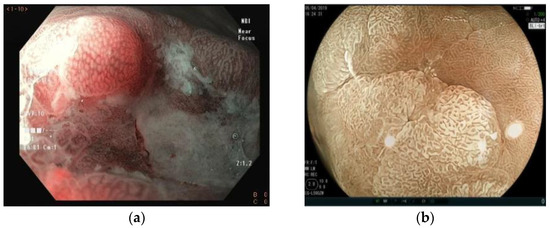

5. Virtual Chromoendoscopy

6. Magnifying Endoscopy

- Fiuza, F.; Maluf-Filho, F.; Ide, E.; Furuya, C.K.; Fylyk, S.N.; Ruas, J.N.; Stabach, L.; Araujo, G.A.; Matuguma, S.E.; Uemura, R.S.; et al. Association between Mucosal Surface Pattern under near Focus Technology and Helicobacter Pylori Infection. World J. Gastrointest. Endosc. 2021, 13, 518–528. [Google Scholar] [CrossRef]

- Uedo, N.; Ishihara, R.; Iishi, H.; Yamamoto, S.; Yamamoto, S.; Yamada, T.; Imanaka, K.; Takeuchi, Y.; Higashino, K.; Ishiguro, S.; et al. A New Method of Diagnosing Gastric Intestinal Metaplasia: Narrow-Band Imaging with Magnifying Endoscopy. Endoscopy 2006, 38, 819–824. [Google Scholar] [CrossRef] [PubMed]

- Yao, K.; Oishi, T.; Matsui, T.; Yao, T.; Iwashita, A. Novel Magnified Endoscopic Findings of Microvascular Architecture in Intramucosal Gastric Cancer. Gastrointest. Endosc. 2002, 56, 279–284. [Google Scholar] [CrossRef]

- Yao, K.; Iwashita, A.; Tanabe, H.; Nishimata, N.; Nagahama, T.; Maki, S.; Takaki, Y.; Hirai, F.; Hisabe, T.; Nishimura, T.; et al. White Opaque Substance within Superficial Elevated Gastric Neoplasia as Visualized by Magnification Endoscopy with Narrow-Band Imaging: A New Optical Sign for Differentiating between Adenoma and Carcinoma. Gastrointest. Endosc. 2008, 68, 574–580. [Google Scholar] [CrossRef]